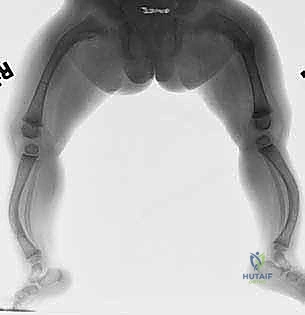

مرحباً بكم في عالم الأمل والتقدم الطبي الرائد في جراحة العظام. يواجه الأطفال المصابون بتخلّق العظم الناقص، والمعروف شعبياً بمرض "العظام الزجاجية"، تحديات يومية هائلة بسبب هشاشة عظامهم، حيث يتعرضون لكسور متكررة وتشوهات قاسية قد تصيب العظام الطويلة (مثل عظم الفخذ والقصبة). هذه الحالة الوراثية المعقدة لا تؤثر فقط على الهيكل العظمي، بل تمتد لتؤثر بشكل كبير وعميق على جودة حياة الطفل، وحالته النفسية، وقدرته على الحركة، واللعب، والنمو بشكل طبيعي أسوة بأقرانه.

في الأطفال المصابين بتخلّق العظم الناقص، توجد طفرة جينية تؤدي إلى نقص كمية الكولاجين أو إنتاج كولاجين مشوه وغير فعال. النتيجة هي عظام هشة جداً لا تتحمل الضغط الميكانيكي العادي. العظام الطويلة، وتحديداً عظم الفخذ (Femur) وعظم القصبة (Tibia)، هي الأكثر عرضة للضرر لأنها تحمل وزن الجسم بأكمله.

مع مرور الوقت والكسور الدقيقة المتكررة، تبدأ هذه العظام في الانحناء والتقوس (Bowing Deformities). هذا الانحناء يغير من الميكانيكا الحيوية للمفاصل (الركبة والورك)، مما يسبب ألماً مزمناً، وصعوبة في المشي، وفي النهاية قد يؤدي إلى فقدان القدرة على الحركة تماماً إذا لم يتم التدخل الجراحي المناسب.

كان عمار يعاني من النوع الثالث من تخلّق العظم الناقص، مع تقوس شديد في عظمي الفخذين (بشكل حرف O) منعه من المشي تماماً، وجعله حبيس الكرسي المتحرك، مع تاريخ من 8 كسور سابقة. تم إجراء عملية بضع العظم المتعدد عبر الجلد وتركيب مسامير فاسييه-دوفال التلسكوبية في كلتا الساقين في جلسة جراحية واحدة بواسطة الدكتور هطيف. اليوم، وبعد 6 أشهر من الجراحة، يمشي عمار مستقلاً لأول مرة في حياته، ولم يتعرض لأي كسر جديد.